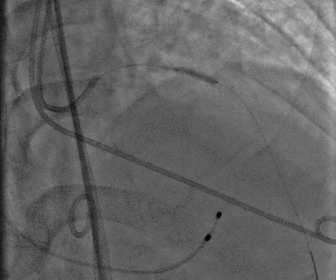

股动脉造影

图片

18f鞘芯预扩张

无鞘法上输送器

股动脉术后造影

术后造影及超声探查未见瓣周漏,跨瓣压差术前54mmHg,术后降为0mmHg,术中及术后未出现相关并发症,手术圆满完成。